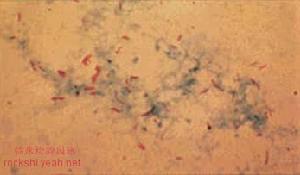

紅細胞計數和血紅蛋白常增高,紅細胞壓積正常或偏高,全血粘度、血漿粘度和血小板聚集率常增高,紅細胞電泳時間延長,血沉一般偏快;動脈血氧飽和度常低於正常,二氧化碳分壓高於正常,呼吸衰竭時更為顯著。在心力衰竭期,可有丙氨酸氨基轉移酶和血漿尿素氮、肌酐、血及尿β2微球蛋白質β2-M)、血漿腎素活性(PRA)、血漿血管緊張素Ⅱ等含量增高等肝腎功能受損表現。合併呼吸道感染時,可有白細胞計數增高。在呼吸衰竭不同階段可出現高鉀、低鈉、低鉀或低氯、低鈣、低鎂等變化。痰細菌培養

以甲型鏈球菌、流感桿菌、肺炎球菌、葡萄球菌、奈瑟球菌,草綠色鏈球菌等多見,近年來革蘭陰性桿菌增多,如綠膿桿菌、大腸桿菌等。X線檢查